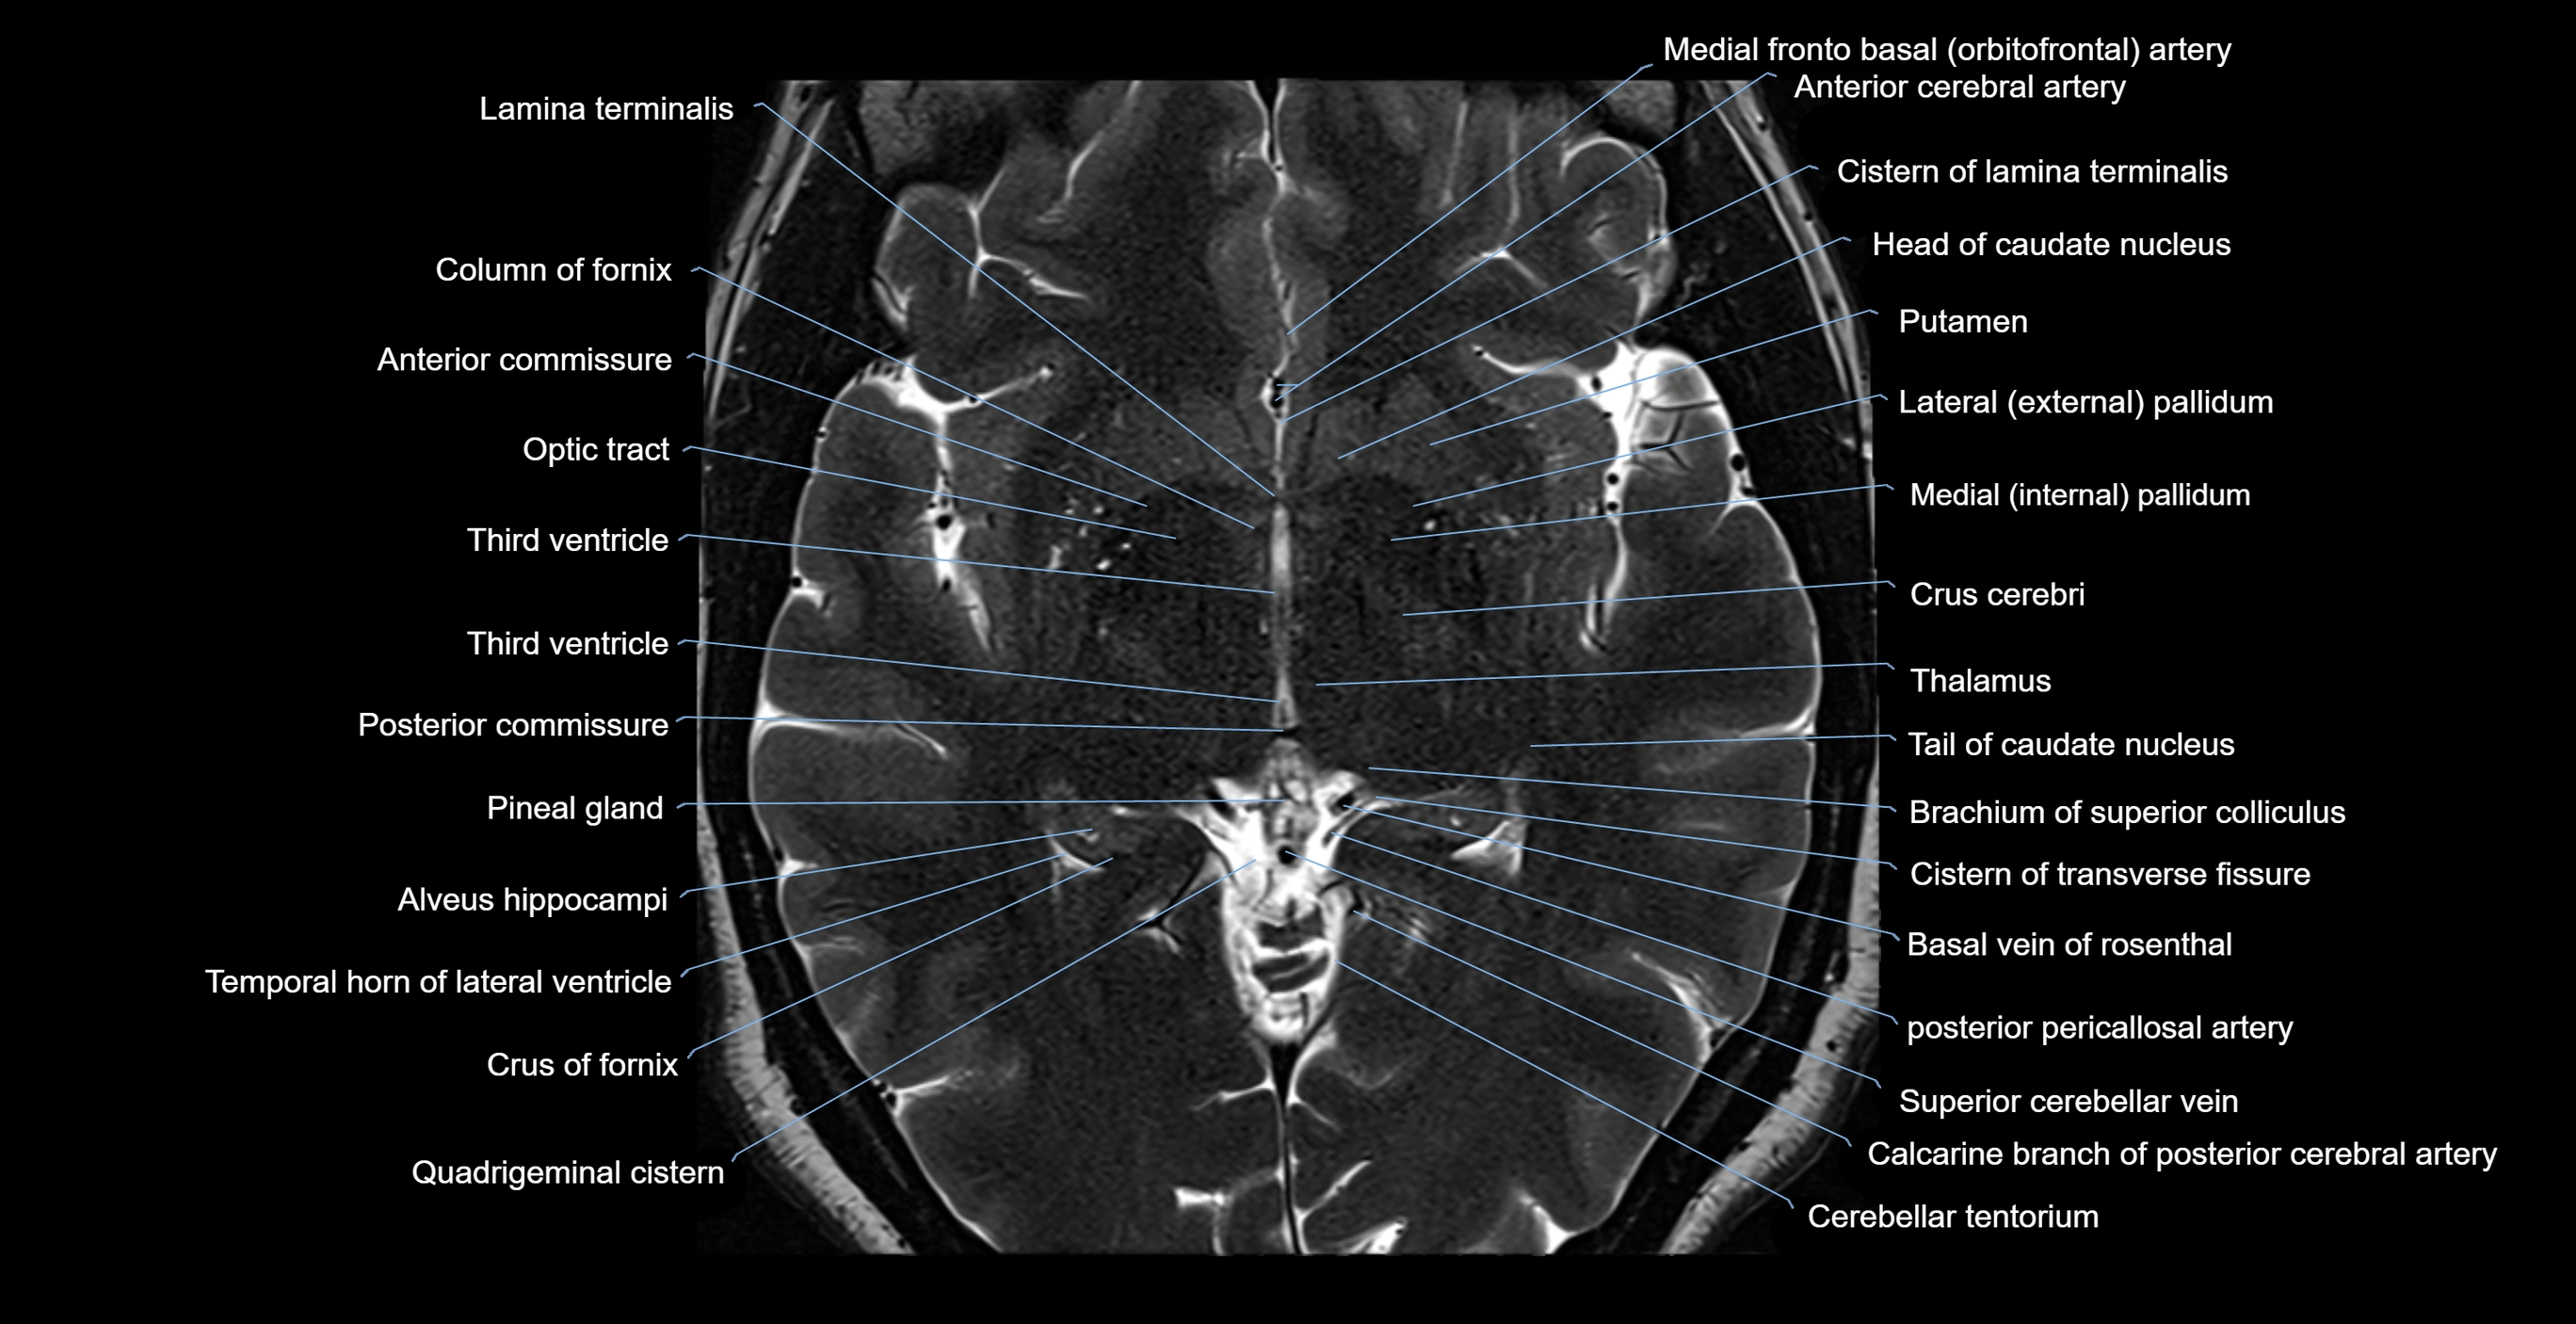

MRI images